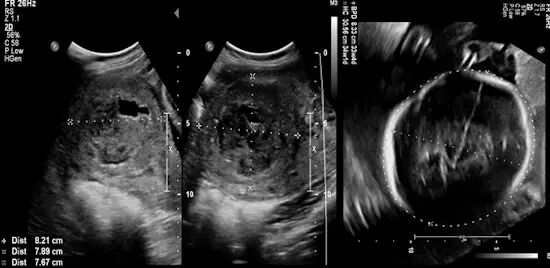

图 3 为患者在肌瘤栓塞术后 8 个月怀孕。超声检查显示为单胎,胎龄 31 周 1 天,与停经日期相符。栓塞术后的肌瘤现在大小为 8.2*7.8*7.6 cm,相比以前呈衰退性改变。胎盘前置,羊水正常。剖宫产后获得健康足月胎儿